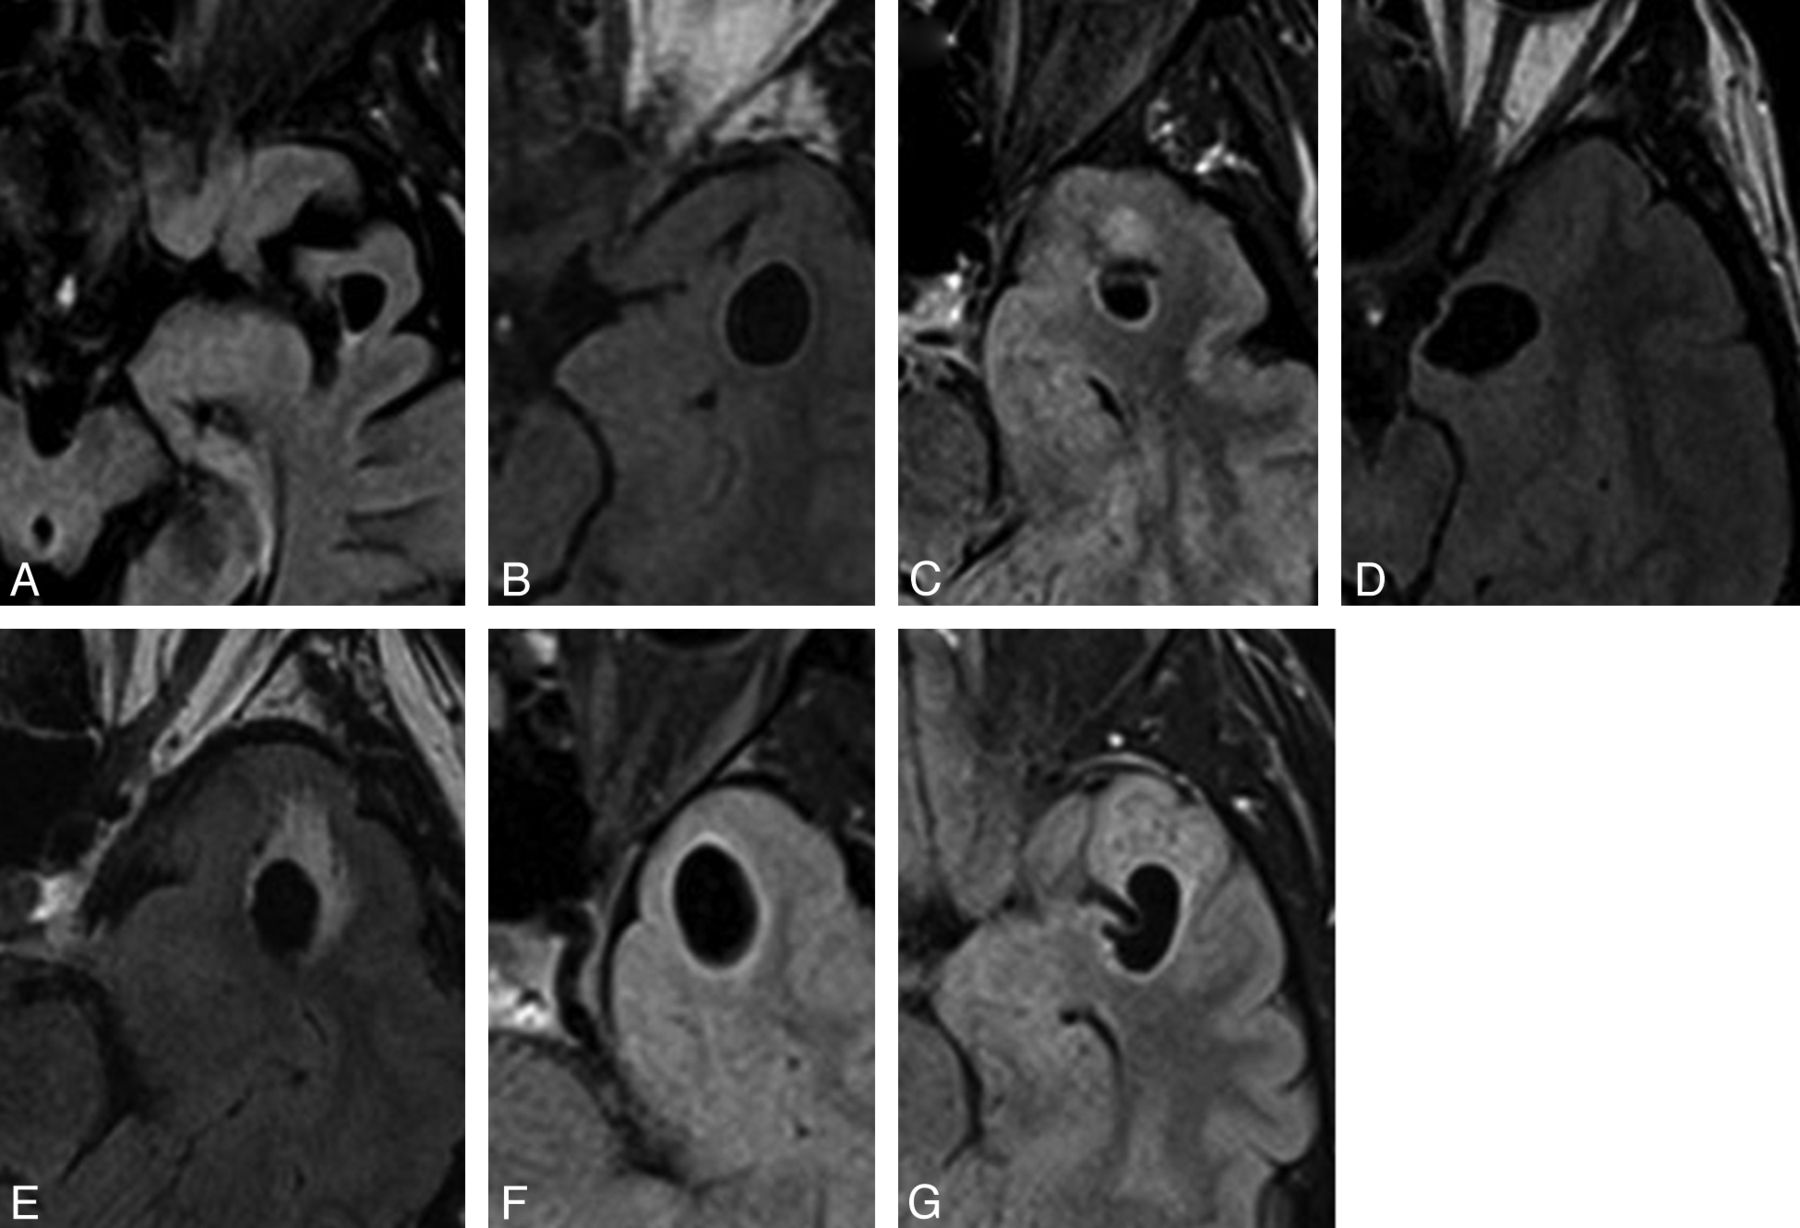

Selected axial FLAIR images of left-sided lesions within the anterior superior temporal gyrus as identified in case 3 (A), 4 (B), 5 (C), 6 (D), 11 (E),13 (F), and 15 (G). All lesions were located adjacent to the SAS. Again, the images illustrate the variability in the degree of surrounding signal change.